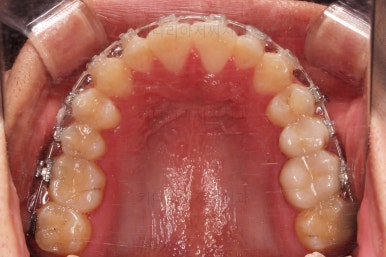

초진 시 입안의 모습입니다.

앞니가 약간 삐뚠 것 말고는 큰 문제는 없어보이네요.

장치를 부착했습니다.

이번 부산연제구교정 환자분이 선택한 장치는 엠파워 클리어라고 하는 자가결찰 세라믹 장치입니다.